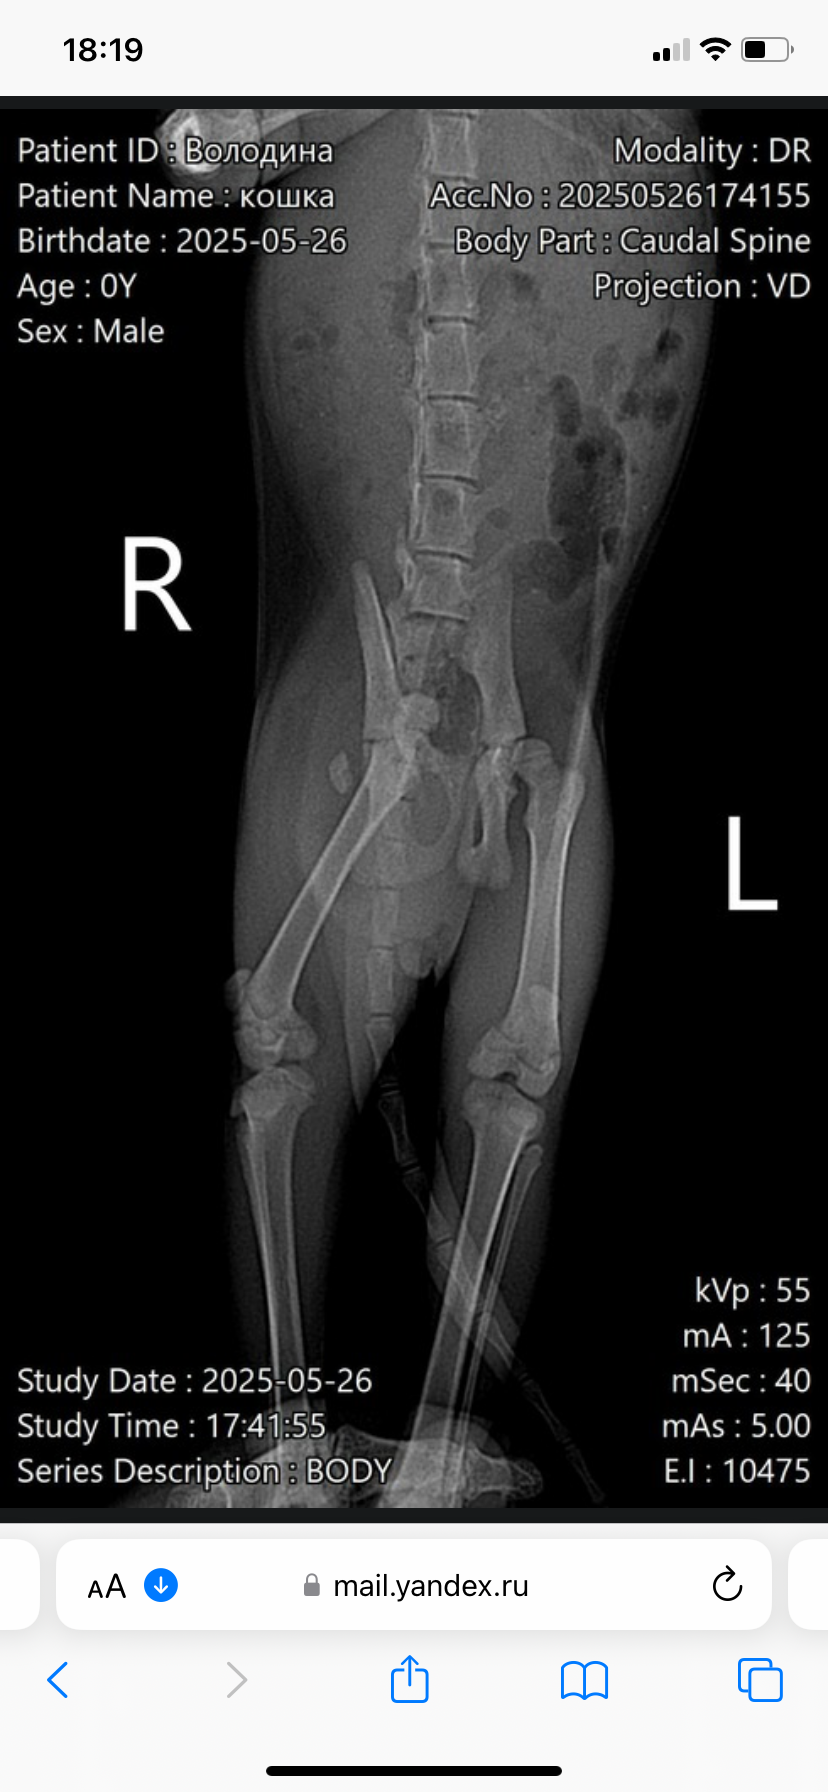

КсенияВолодина

IMG_3795.jpeg

А какую операцию предлагают с вывихом? Что они за 10 там делать собираются?